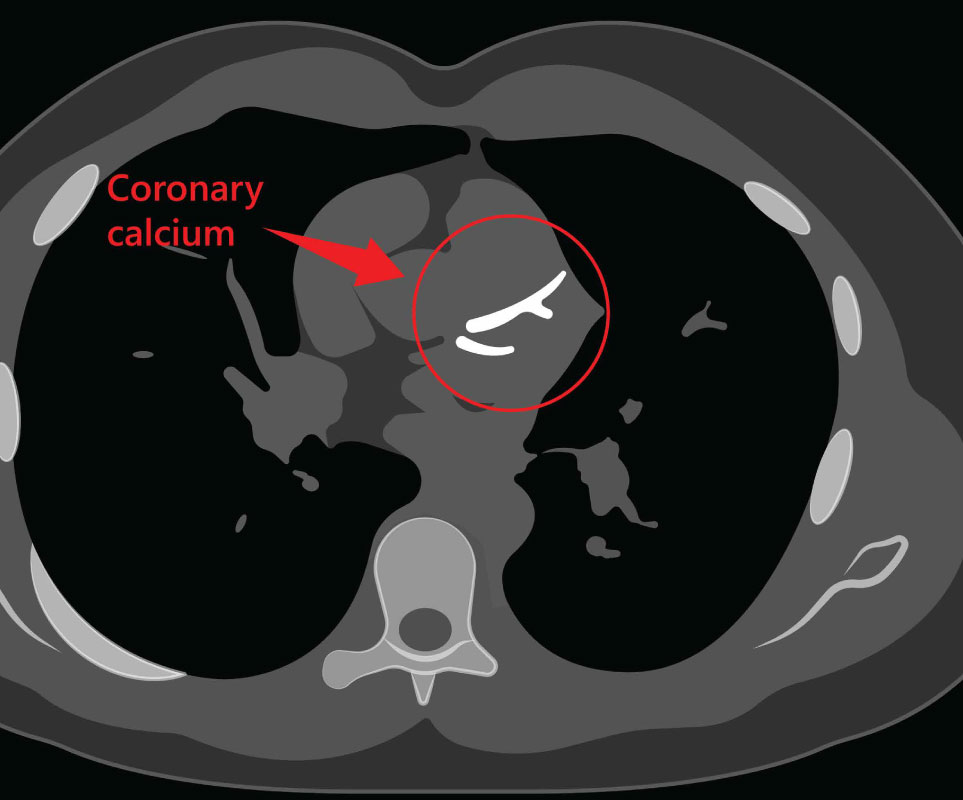

Coronary Artery Calcium Scoring Current Status And Future Directions

Coronary Artery Calcium Scoring: Its Practicality And Clinical Utility

calcium coronary artery scoring significant cardiovascular clinical practicality ccjm

calcium coronary artery calcification plaque amount scanner

Coronary Artery Calcium Scoring - A Risk Predictor

Coronary Artery Calcium Scoring

calcium coronary artery scoring screening heart disease

Coronary Artery Calcium Scoring — Is It Useful? - Dr Ross Walker

Calcium Score / CT Heart Scan

calcium coronary atherosclerosis arteriosclerosis ct arteries treatment diagnosis cardiology

Coronary Calcium Score - Capital Heart Centre

CT Calcium Score Scan | Perth Radiological Clinic

calcium score coronary